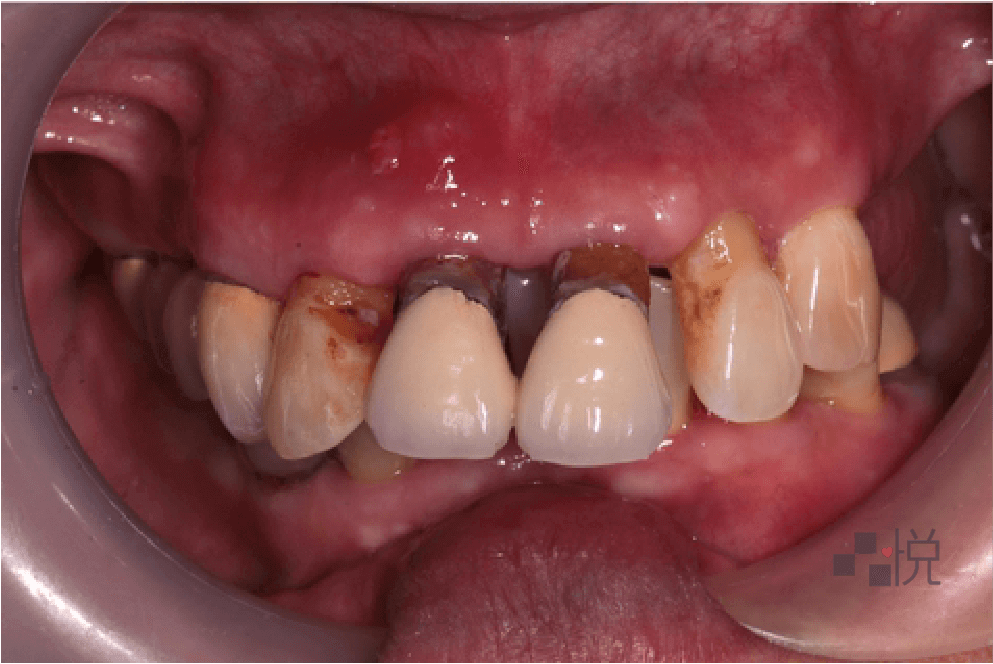

住在附近的張女士(化名)以前覺得牙齒痛了再處理就好,不過隨著年紀大,牙齒位置越來越歪,甚至會嚇到人,且不時有腫痛情形。

缺牙也讓生活品質下降、身體狀況惡化更快,於是決定來找饒醫師好好治療整理一番。

經由診斷,張女士多年的牙周病造成牙齒「病理性位移」,不只是外觀完全改變,還會發出臭味、到處不時流膿發炎。牙周病發病前期都不大會痛,發現時往往已經非常嚴重。

由於牙周問題嚴重,先由牙周醫師做全口牙周雷射治療,並拔除沒有救的牙齒。